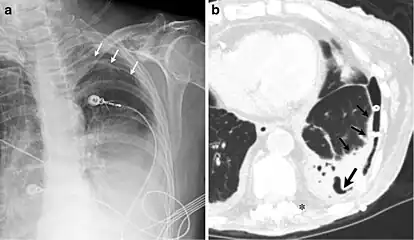

A fibrothorax can typically be diagnosed by taking an appropriate medical history in combination with the use of appropriate imaging techniques such as a plain chest X-ray or CT scan.[3] These imaging techniques can detect fibrothorax and pleural thickening that surround the lungs.[7] The presence of a thickened peel with or without calcification are common features of fibrothorax when imaged.[3] CT scans can more readily differentiate whether pleural thickening is due to extra fat deposition or true pleural thickening than X-rays.[3]

If a fibrothorax is severe, the thickening may restrict the lung on the affected side causing a loss of lung volume.[7] Additionally, the mediastinum may be physically shifted toward the affected side.[3] A reduction in the size of one side of the chest (hemithorax) on an X-ray or CT scan of the chest suggests chronic scarring.[6] Signs of the underlying disease causing the fibrothorax are also occasionally seen on the X-ray.[6] A CT scan may show features similar to those seen on a plain X-ray.[7] Lung function testing typically demonstrates findings consistent with restrictive lung disease.[6]

CXR of an individual affected by fibrothorax (consequence of tuberculosis)

Extensive left-sided fibrothorax

Chest radiograph displaying inhomogeneous opacification of the left half of the chest that is fibrothorax